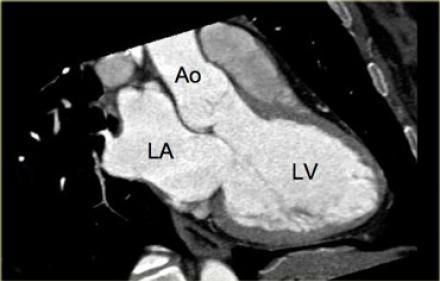

what doe this image show and what type of test is it?

MRI

what are the different planes of MRI scans

short axis (parasternal)

long axis (parasternal)

4 chamber ( LA LV RA RV )

2 chamber ( LA LV )

3 chamber ( LV LA A )